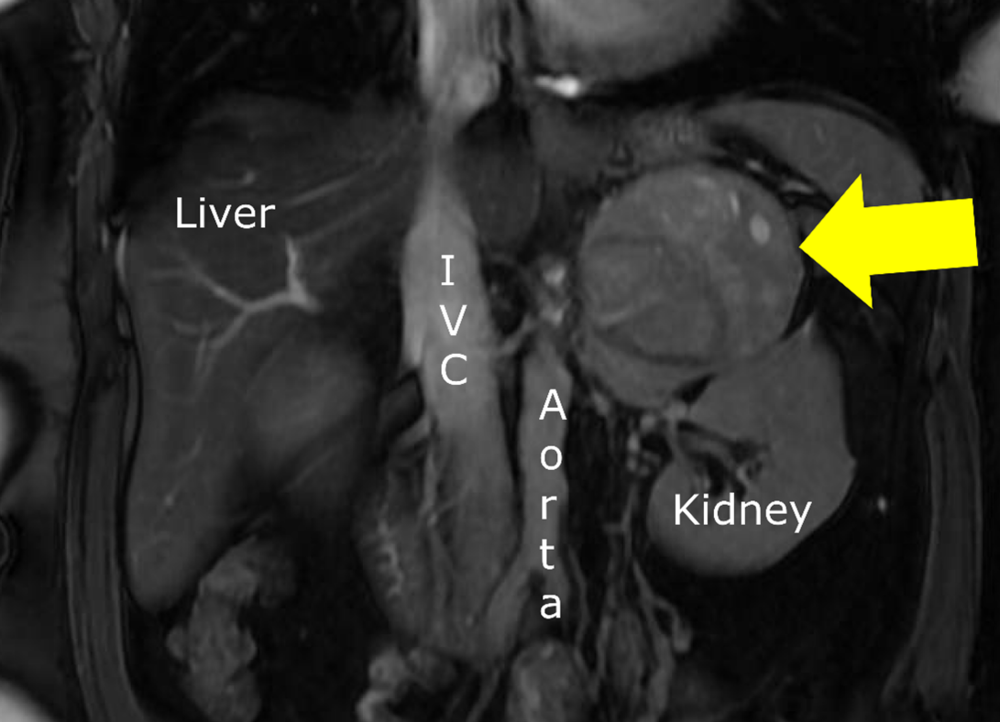

Figure. MRI of a left adrenal cancer (arrow) which produced very high levels of DHEA-S causing virilization in a woman with excessive facial hair (hirsutism), irregular menses, voice changes and other male characteristics.